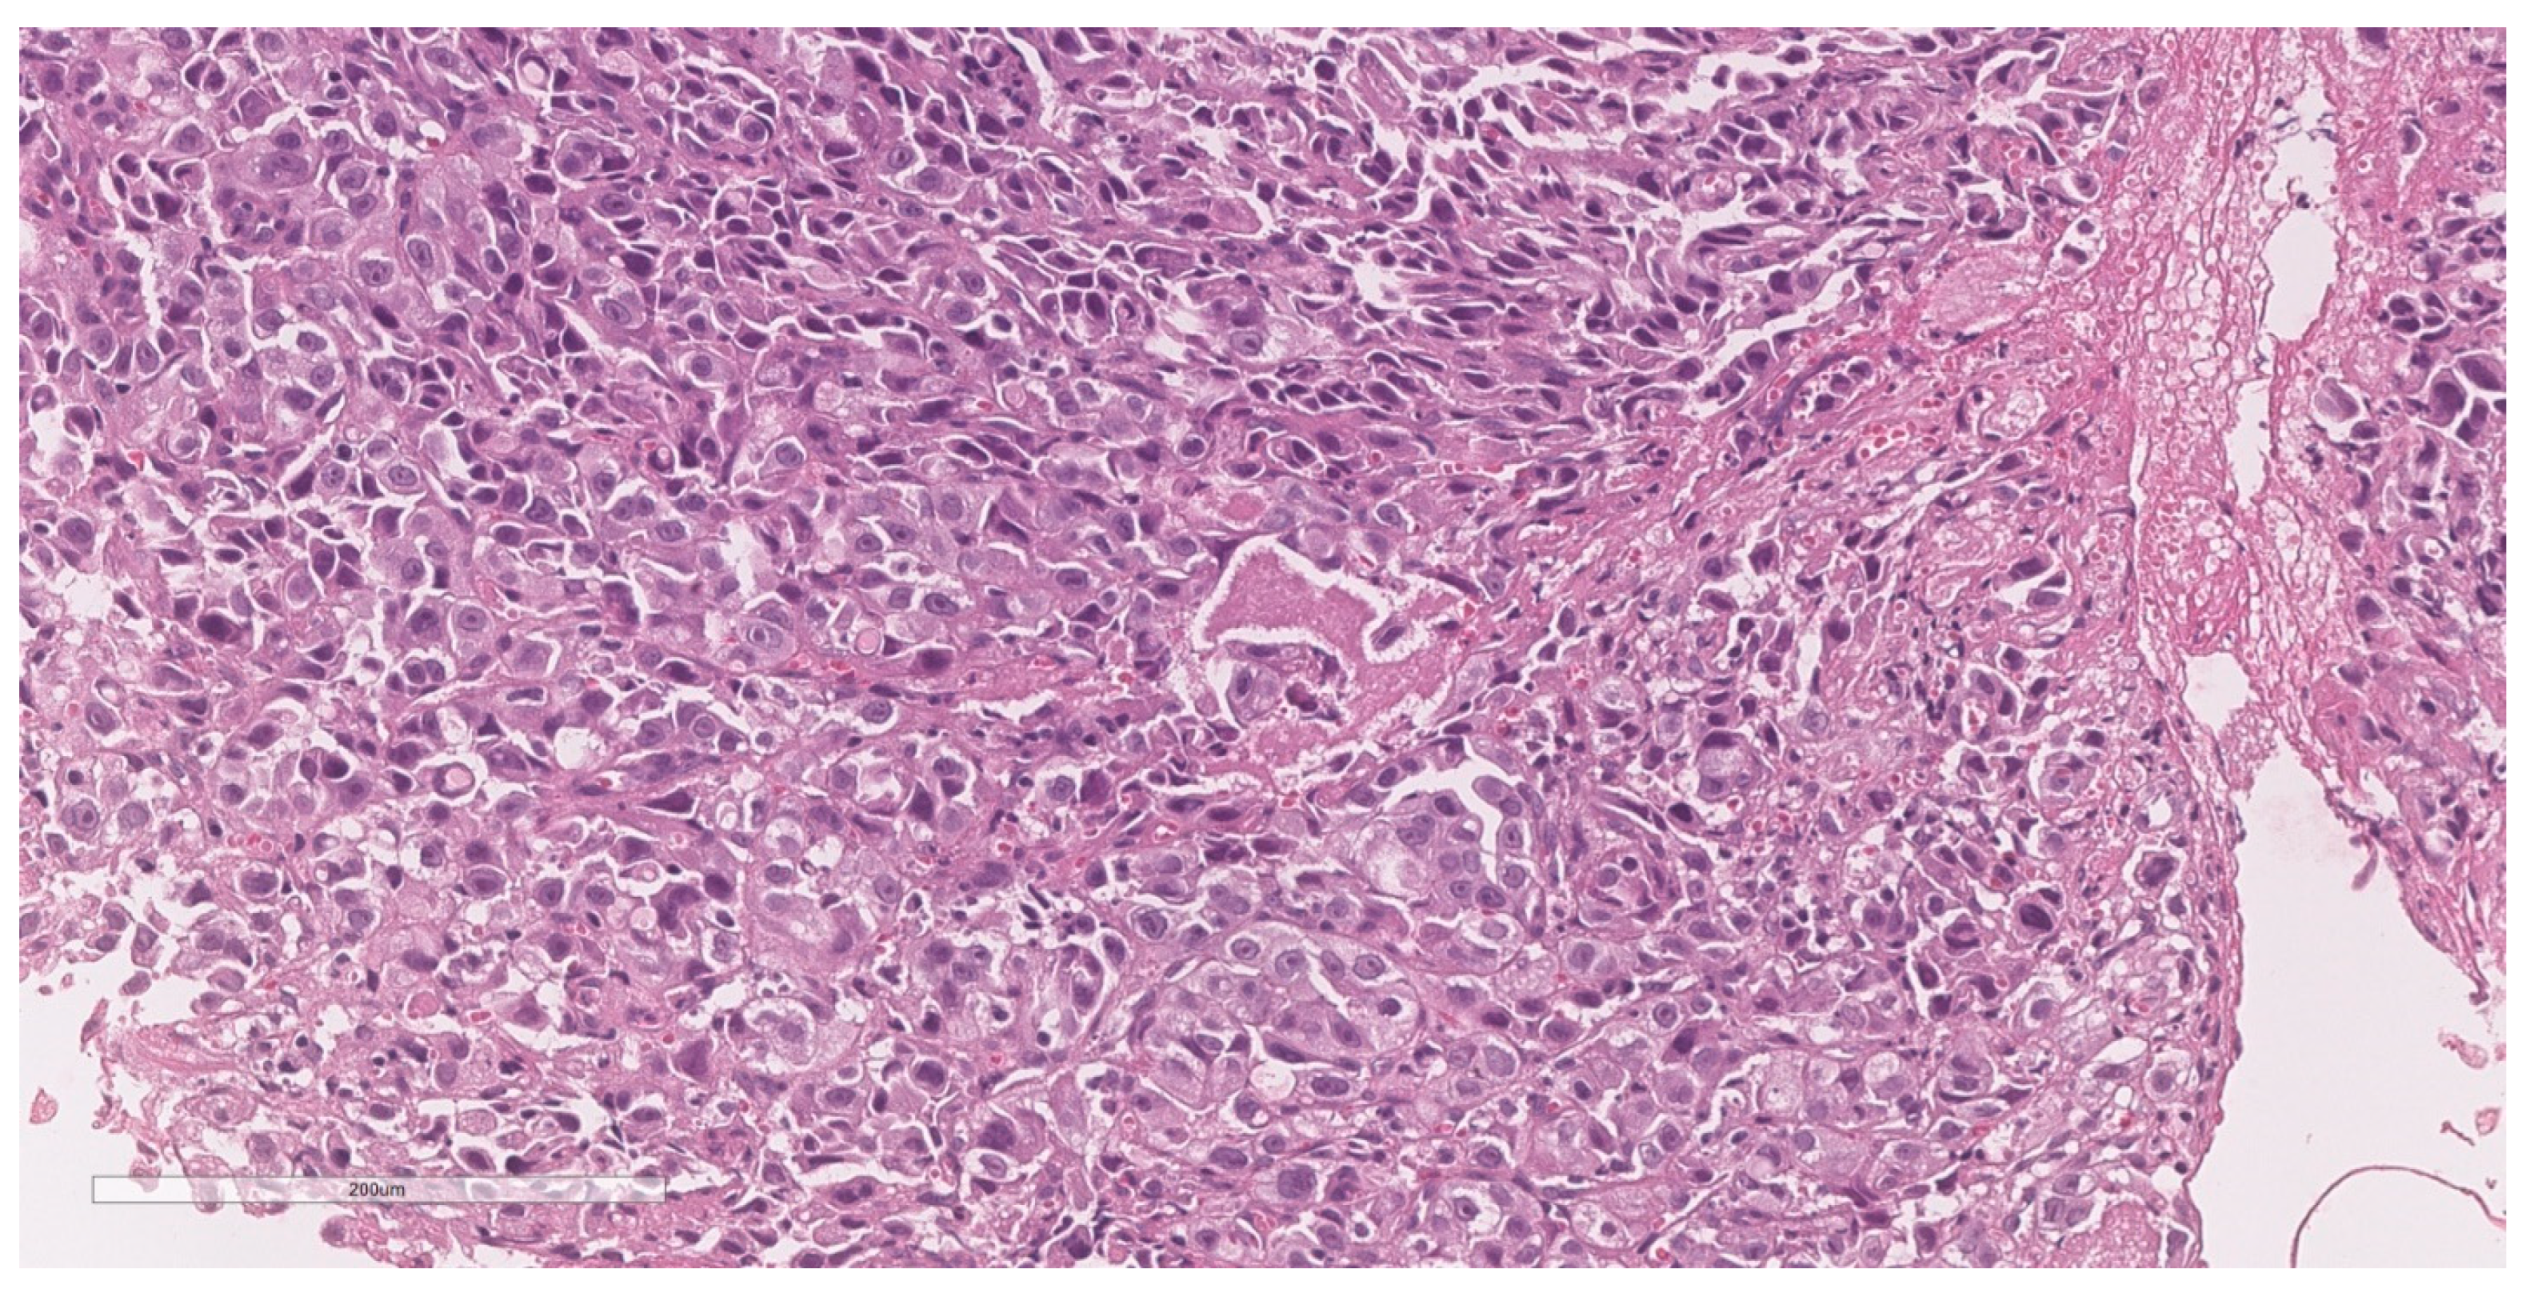

2.3. Surgical Procedure and Pathological Findings